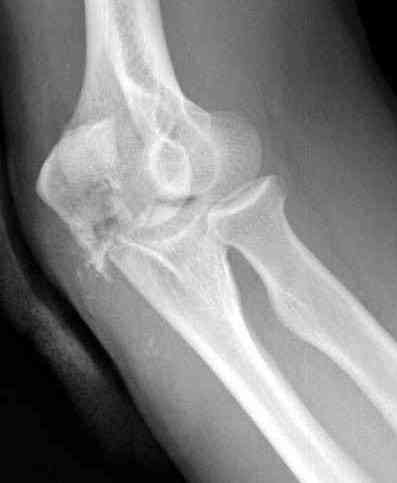

Снимки вот еще какие есть (наши лаборанты пытались сделать что то)

Good day dears colleagues! You presentated only one x-ray proection - lateral- of elbow.Accorden this I thing that this isn't avulsion fracture of olecranon,as usually can to see.This is Monteggia like fracture with subluxation of radial head.If

you can show AP x-ray or more more better CT elbow

Снимок, действительно, "не очень". Но глядя на него почему-то возникает очень сильное ощущение, что там и венечный отросток сломан тоже. Что ситуацию здорово усложняет. Причём перелом венечного "III типа" - очень крупный фрагмент, отломанный под самое его основание. А это (без фиксации) уже грозит задней, а возможно - и фронтальной (вальгусной/варусной) нестабильностью.

При самом большом к Вам уважении, Сергей Анатольевич, не соглашусь. У меня, после того, как добавили "прямой" снимок, сомнений не осталось. Венечный сломан наверняка. Но чтобы судить, насколько это критично для стабильности, нужно иметь строго боковую проекцию. И при этом помнить, что на него крепятся медиальные связки.

Прикрепляю снимок, где обведен фрагмент, несущий на себе венечный отросток (весь он смещён с этим фрагментом или частично - без качественной боковой проекции судить сложно), и отдельно на снимке обведено "ложе", от которого он сместился.